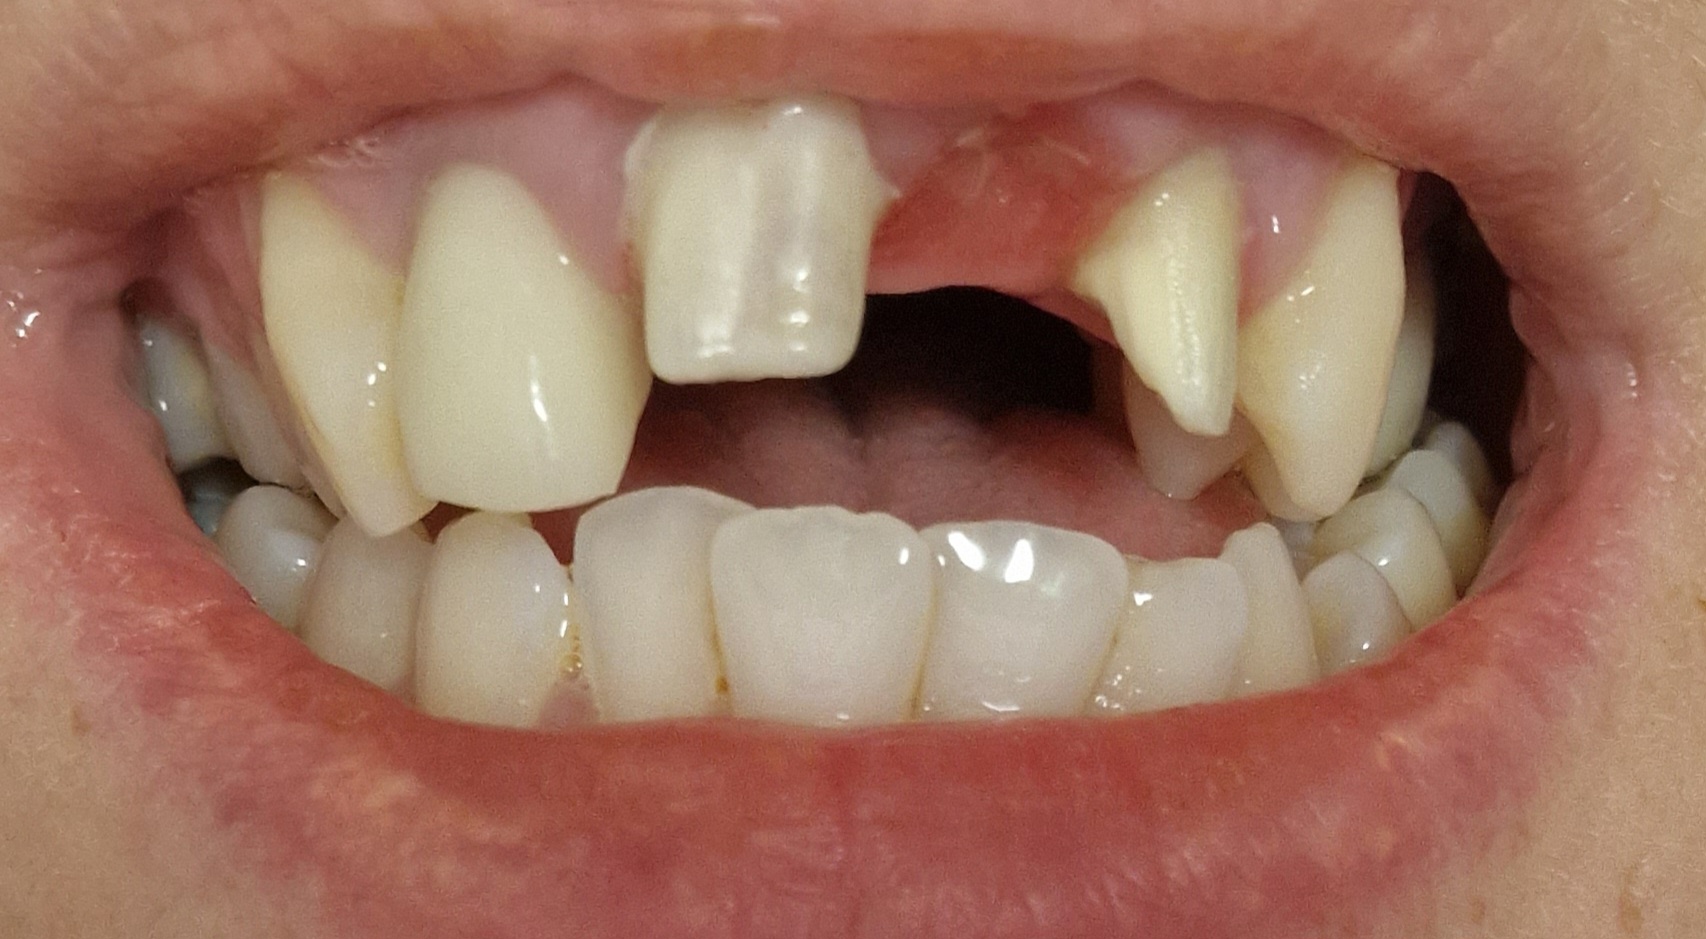

Kort na mijn bericht op dit forum ben ik weer bij mijn eigen tandarts geweest met de flinke ontstekingen en een wortelkanaalbehandeling wat nog afgemaakt diende te worden. Echter weigerde hij zelf nog foto's te maken van de tand waardoor abcessen ontstonden. "Ik weet bijna zeker dat het door de andere tand komt (met de wortelkanaalbehandeling)". Besproken om nieuwe kronen te maken aangezien er inderdaad alles fout aan was. Ze waren ook te strak ertussen geduwd wat het een en ander kapot heeft zitten duwen waardoor waarschijnlijk de ellende is begonnen. Ook te lang, etc etc. Nu had ik 2 weken daarna de afspraak voor opnieuw te happen en verwijderen van de kronen. Nu kwam tijdens het wringen/trekken van de kronen een van mijn voortanden mee 🥴... ik schrok me echt kapot! Na alle ellende nu ook een goede tand verloren! Verder gegaan met het plaatsen van noodkronen/brug. Echter heb ik momenteel al de definitieve kronen (laten plaatsen met tijdelijk cement..)

Morgen terug voor aanpassingen. Hij beloofde de noodkronen te maken en aan te passen totdat ik tevreden was én pas dan de definitieve precies zo na te laten maken. Ook extra voor gehapt. Echter zijn de noodkronen precies weer zo lelijk geworden als de eerste definitieve kronen. Gelukkig wel een stukje korter maar weer zo hoog geplaatst, de tandvleesbogen lelijk, en weer veel te bol..

( zie foto's met poging 2)

De incisale (snijlijn) komt nu beter overeen met uw oorspronkelijke stand. U trekt uw lippen nu in een gedwongen onnatuurlijke stand waardoor alles er ook anders uit ziet. De Cervicale grens( bovenkant tegen tandvlees) is iets anders dan oorspronkelijk maar dat kan gebeuren afhankelijk v hoeveel men heeft weg geslepen. u trekt uw lip ook hoger op, hoger dan dat het in een normale stand zou zijn. Als uw lip normaal zou hangen denk ik dat u niet zult zien dat de cervicale lijn zo hoog zou zijn. Ik zou een half jaar wachten met definitief cementeren v d kronen, en pas als u helemaal tevreden en klachtenvrij bent def cementeren. Ik schrik dat een tand getrokken is bij het verwijderen v d kronen. Vraag mij dan ook af of uw parodontium ( ophanging tandvlees) wel gezond genoeg is om kronen te rechtvaardigen. Zou dan ook de x-foto v voor aanvang behandeling willen zien. U kunt een kopie digitaal vragen. Bij het afmaken v d wkb worden nieuwe x-foto gemaakt, vraag die dan ook gelijk en de x-foto v d dienst. Ben benieuwd wat er op te zien is.

Samen met mijn tandarts besproken om nieuwe kronen te laten maken. Telkens gingen aanpassingen mis/er leek niet goed geluisterd te worden. Zo zijn er in totaal zeker 6x nieuwe kronen gemaakt.

Nu ben ik afgelopen maand (Oktober) voor het laatst bij de tandarts geweest om te bespreken over de kronen die ik nu draag, ook deze zijn alsnog met tijdelijk cement vast gezet. Kun je na gaan dat ik al vanaf Sept 2022 bezig ben..

Over deze kronen ben ik nog steeds niet te vreden: kleur wijkt enorm af, vooral in een bepaald daglicht. Ook de boog vind ik nog steeds niet mooi, tandvlees (papil) komt niet mooi uit, erg onsymmetrisch..

Daarbij kronen ook erg bol, boven bij het tandvlees steekt de kroon ver uit tov het tandvlees.

Dit met de tandarts besproken, hij zegt dat hij er niks aan kan veranderen zowel niet aan de tandvleesbogen als de bolling. Het tandvlees zou weg zijn ivm het verlies van de 11. Hij geeft aan dat ik het moet leren accepteren dat het nu zo is, maar ik vind het echt vreselijk.

Daarbij viel mij op dat de 21 erg 'grijzig' oogt soms wanneer ik in een spiegel kijk elders. Nu scheen ik eens met een lampje van achteren en zie ik donker/zwart binnen in de kroon. Alsof mijn eigen tand zwart/rot is..